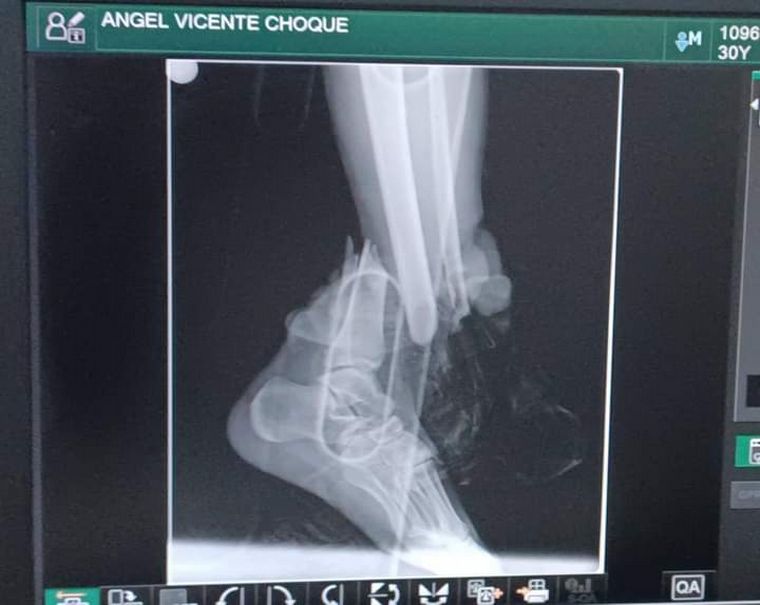

Ángel, de 30 años, iba camino a trabajar y el motociclista Víctor Quispe Herrera lo chocó de atrás y le provocó una fractura expuesta en la pierna izquierda.

Tras ser atropellado por un motociclista, aparentemente alcoholizado, que le fracturó la tibia y peroné.

El argentino fue derivado al Hospital Dr. Roberto Galindo Terán, al norte del país en una zona amazónica y cerca de la triple frontera con Brasil y Perú. Allí fue atendido en primeros auxilios y le instalaron unos fijadores de urgencia para evitar que perdiera la pierna. Por mantenerlo internado, la familia desembolsó más de $400.000, pero el monto final es mucho más alto.